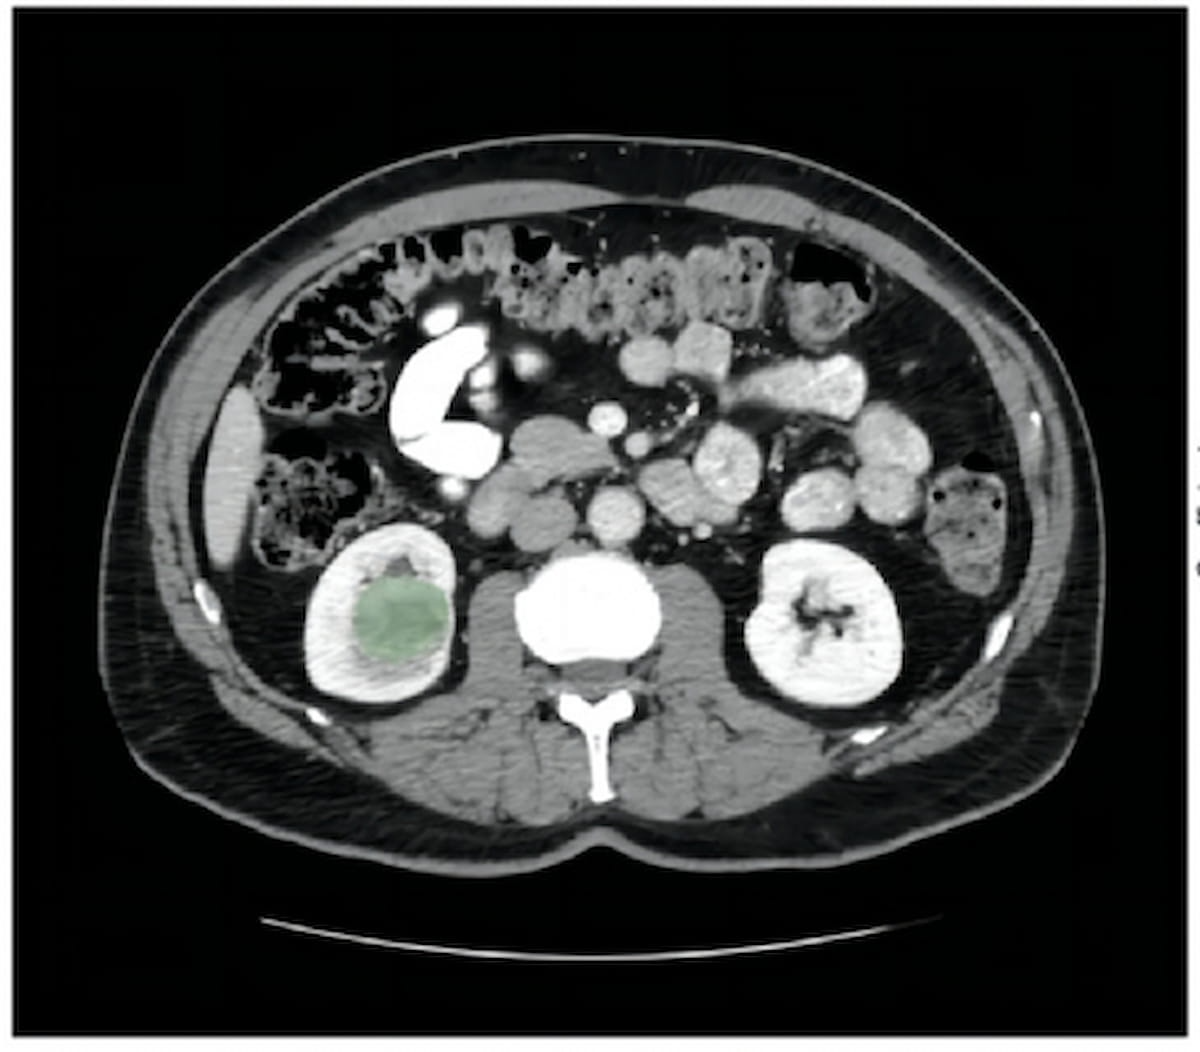

Emerging research suggests that a computed tomography (CT)-based radiomics model can predict FOXM1 expression and is independently prognostic for clear cell renal cell carcinoma.